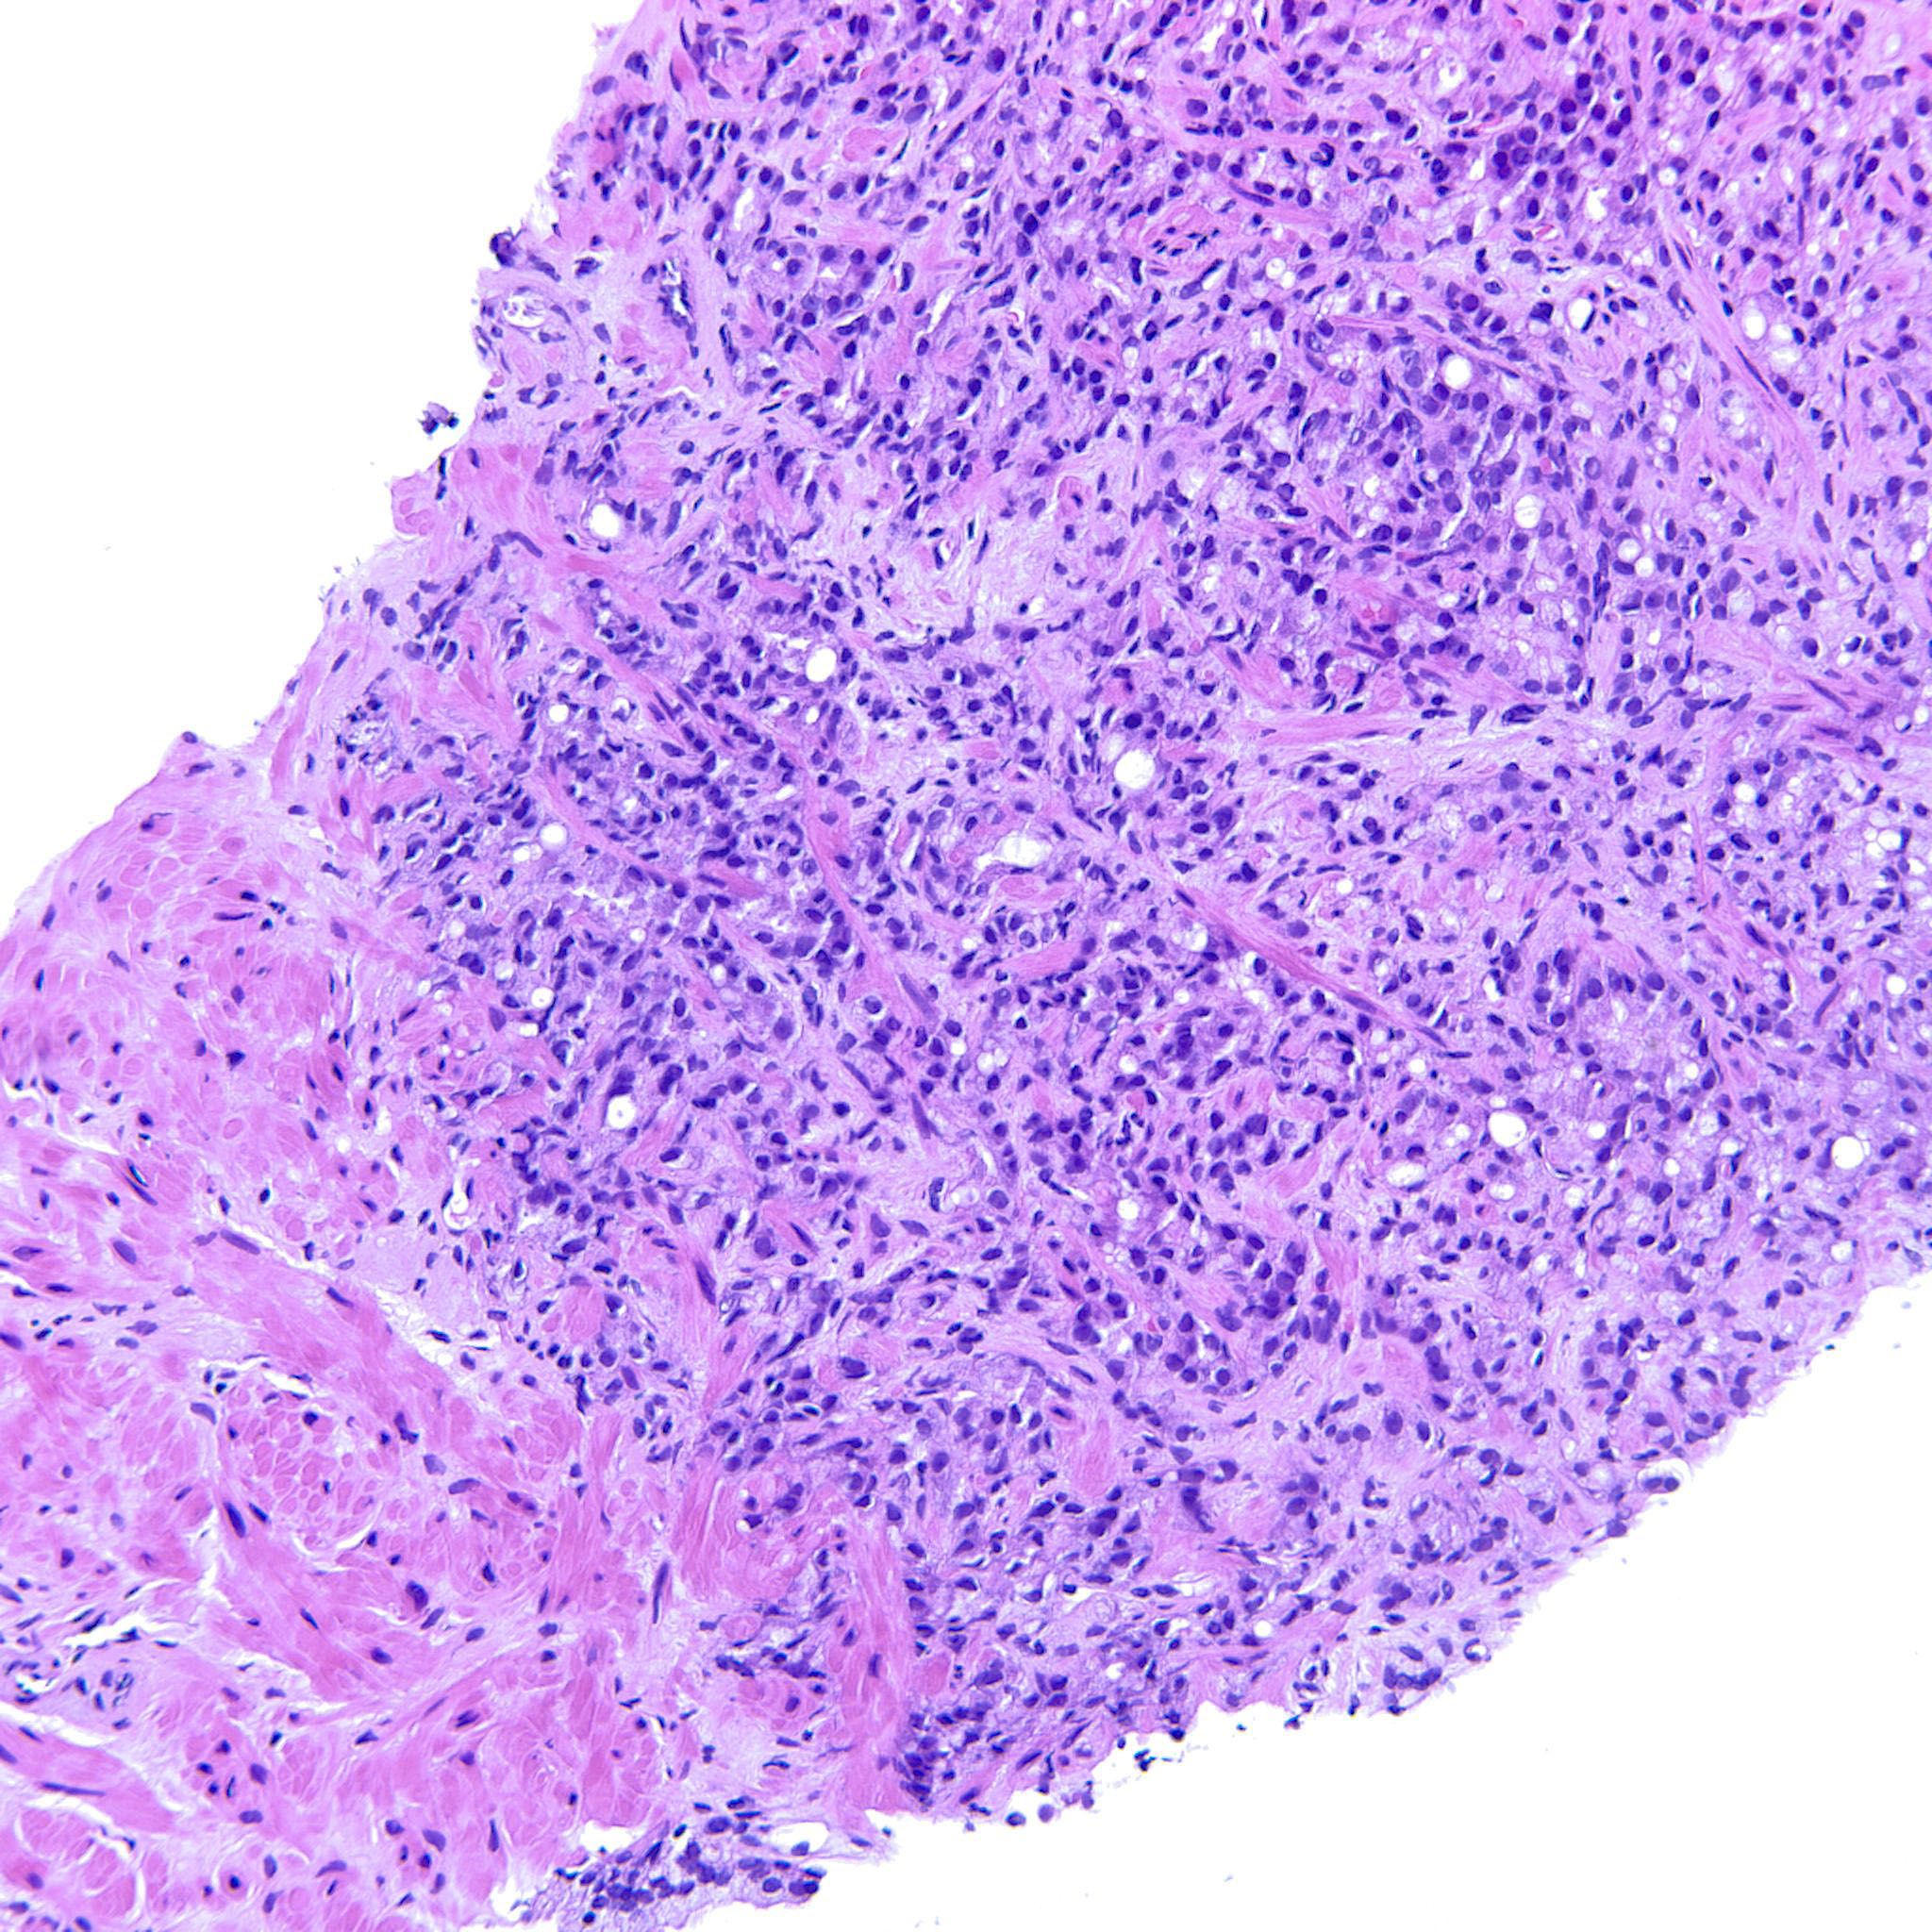

Prostate cancer grading

Case ID: 744